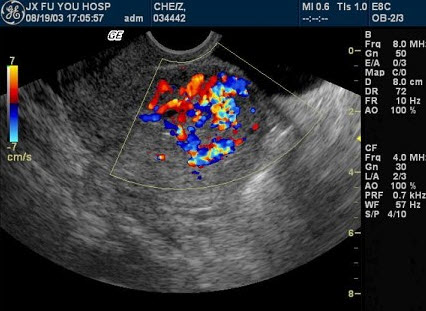

E.A+C